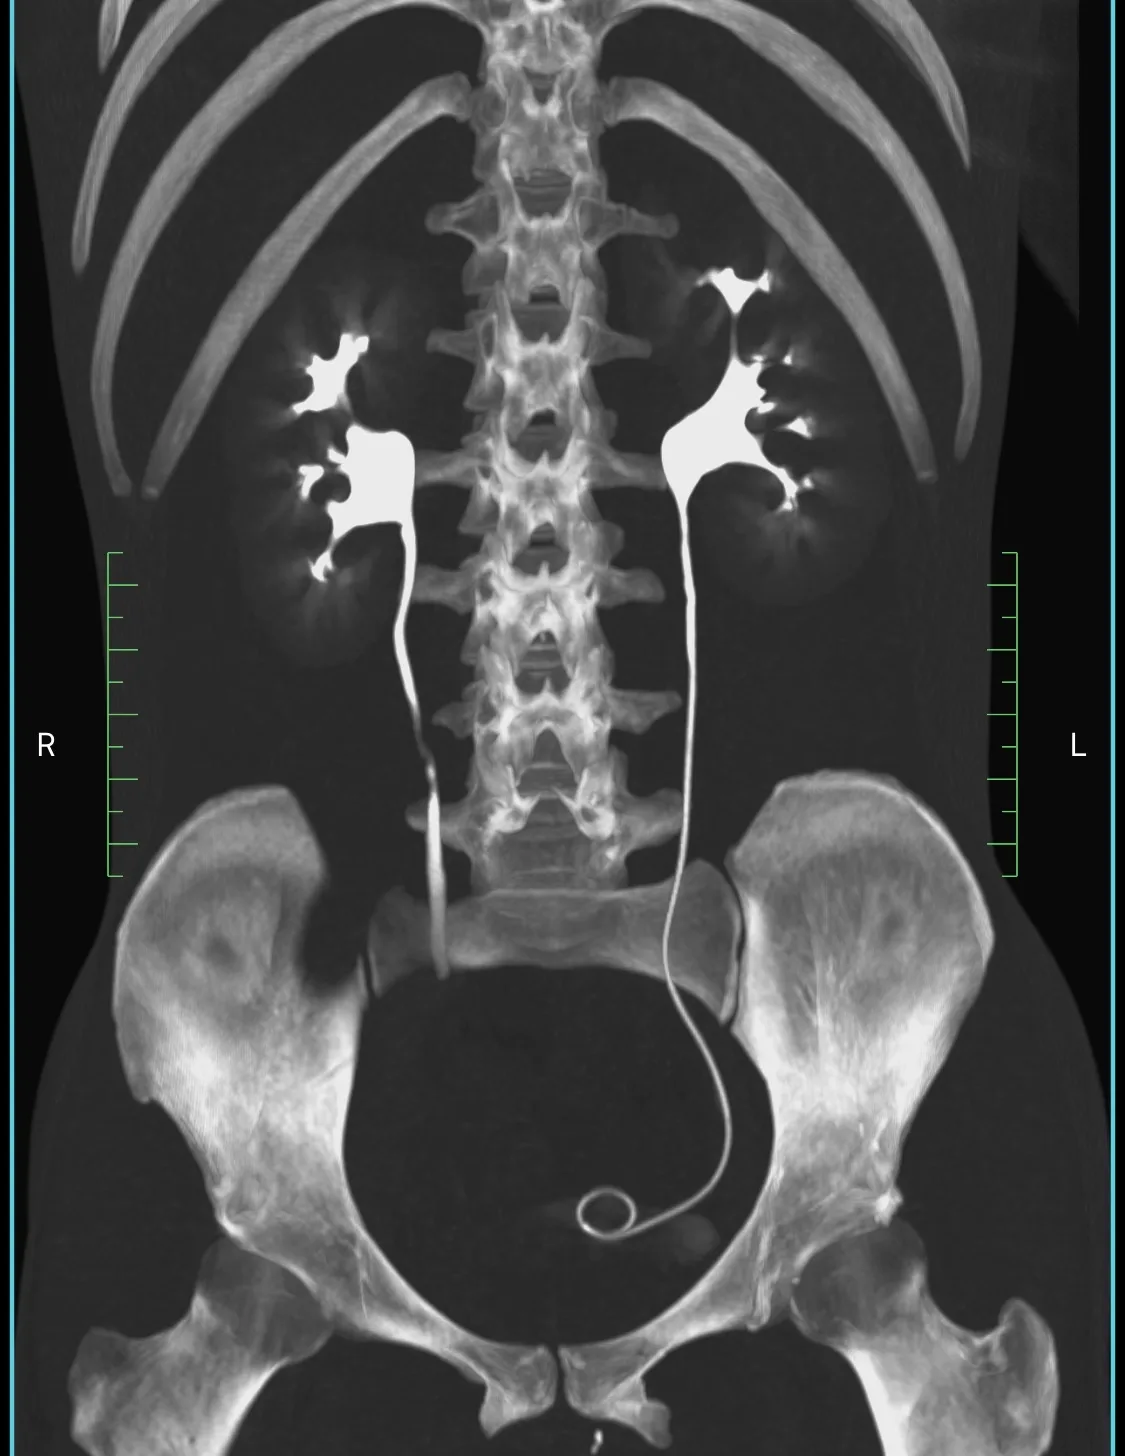

Пациент 27 лет. Две недели назад ударно-волновая литотрипсия. Неделю назад резкое повышение температуры тела, боли в боку. Повторная госпитализация. Установлен стент в левый мочеточник. Нарушения оттока мочи нет. На компьютерных томограммах левосторонний бактериальный нефрит, в верхнем полюсе левой почки – то, что иногда называют карбункул: воспалительный инфильтрат без формирования абсцесса (в англоязычной литературе называется нефрония). Принято решение продолжать антибиотикотерапию.